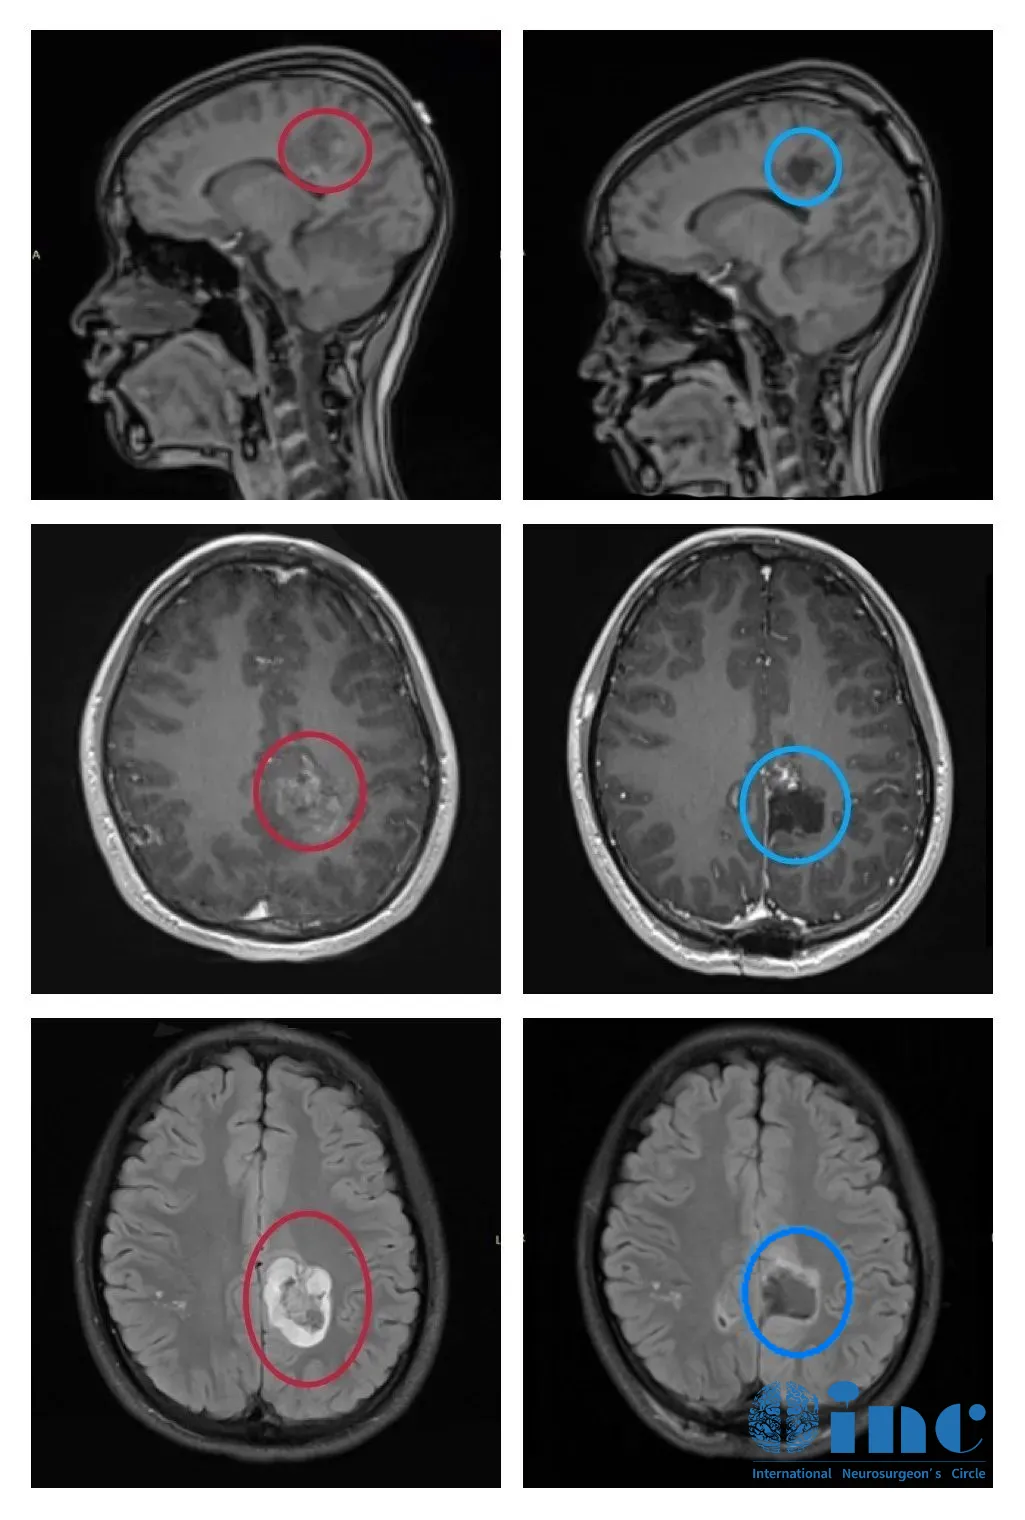

术前术后影像对比

(红色为术前,蓝色为术后)

手术后第二天出ICU,可以自行持筷用餐且能在医护人员搀扶下下地行走。术后第三天,已能自行下地行走,平衡力正常,且没有其他新发神经症状出现。术后配合医院康复训练,1周后即出院。